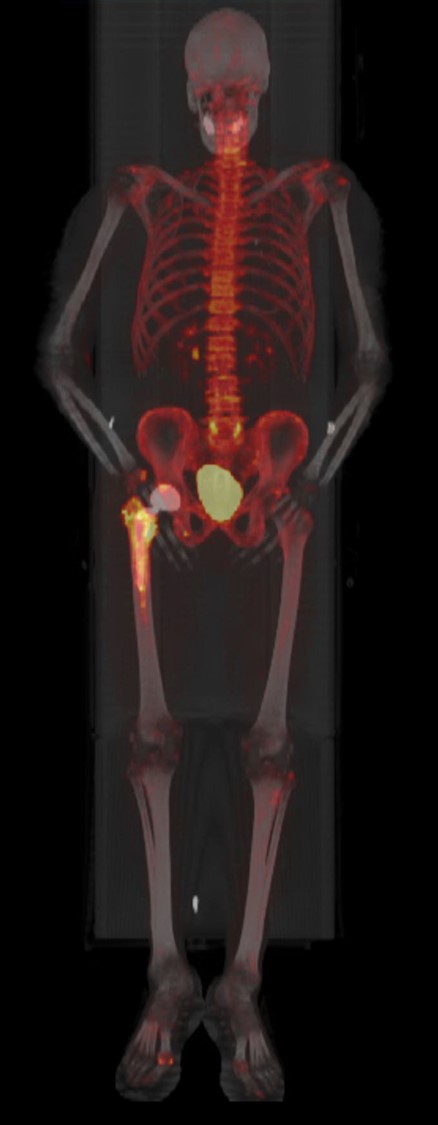

| 49 year-old women with right hip hemiarthroplasty. Maximum intensity projection images of CT with bone window (A), NaF PET (B), and fused PET-CT image (C) demonstrate right femoral prosthesis with intense NaF uptake in the proximal femur surrounding the prosthesis, representing reparative bone remodeling. This can last for years and is not pathological. |